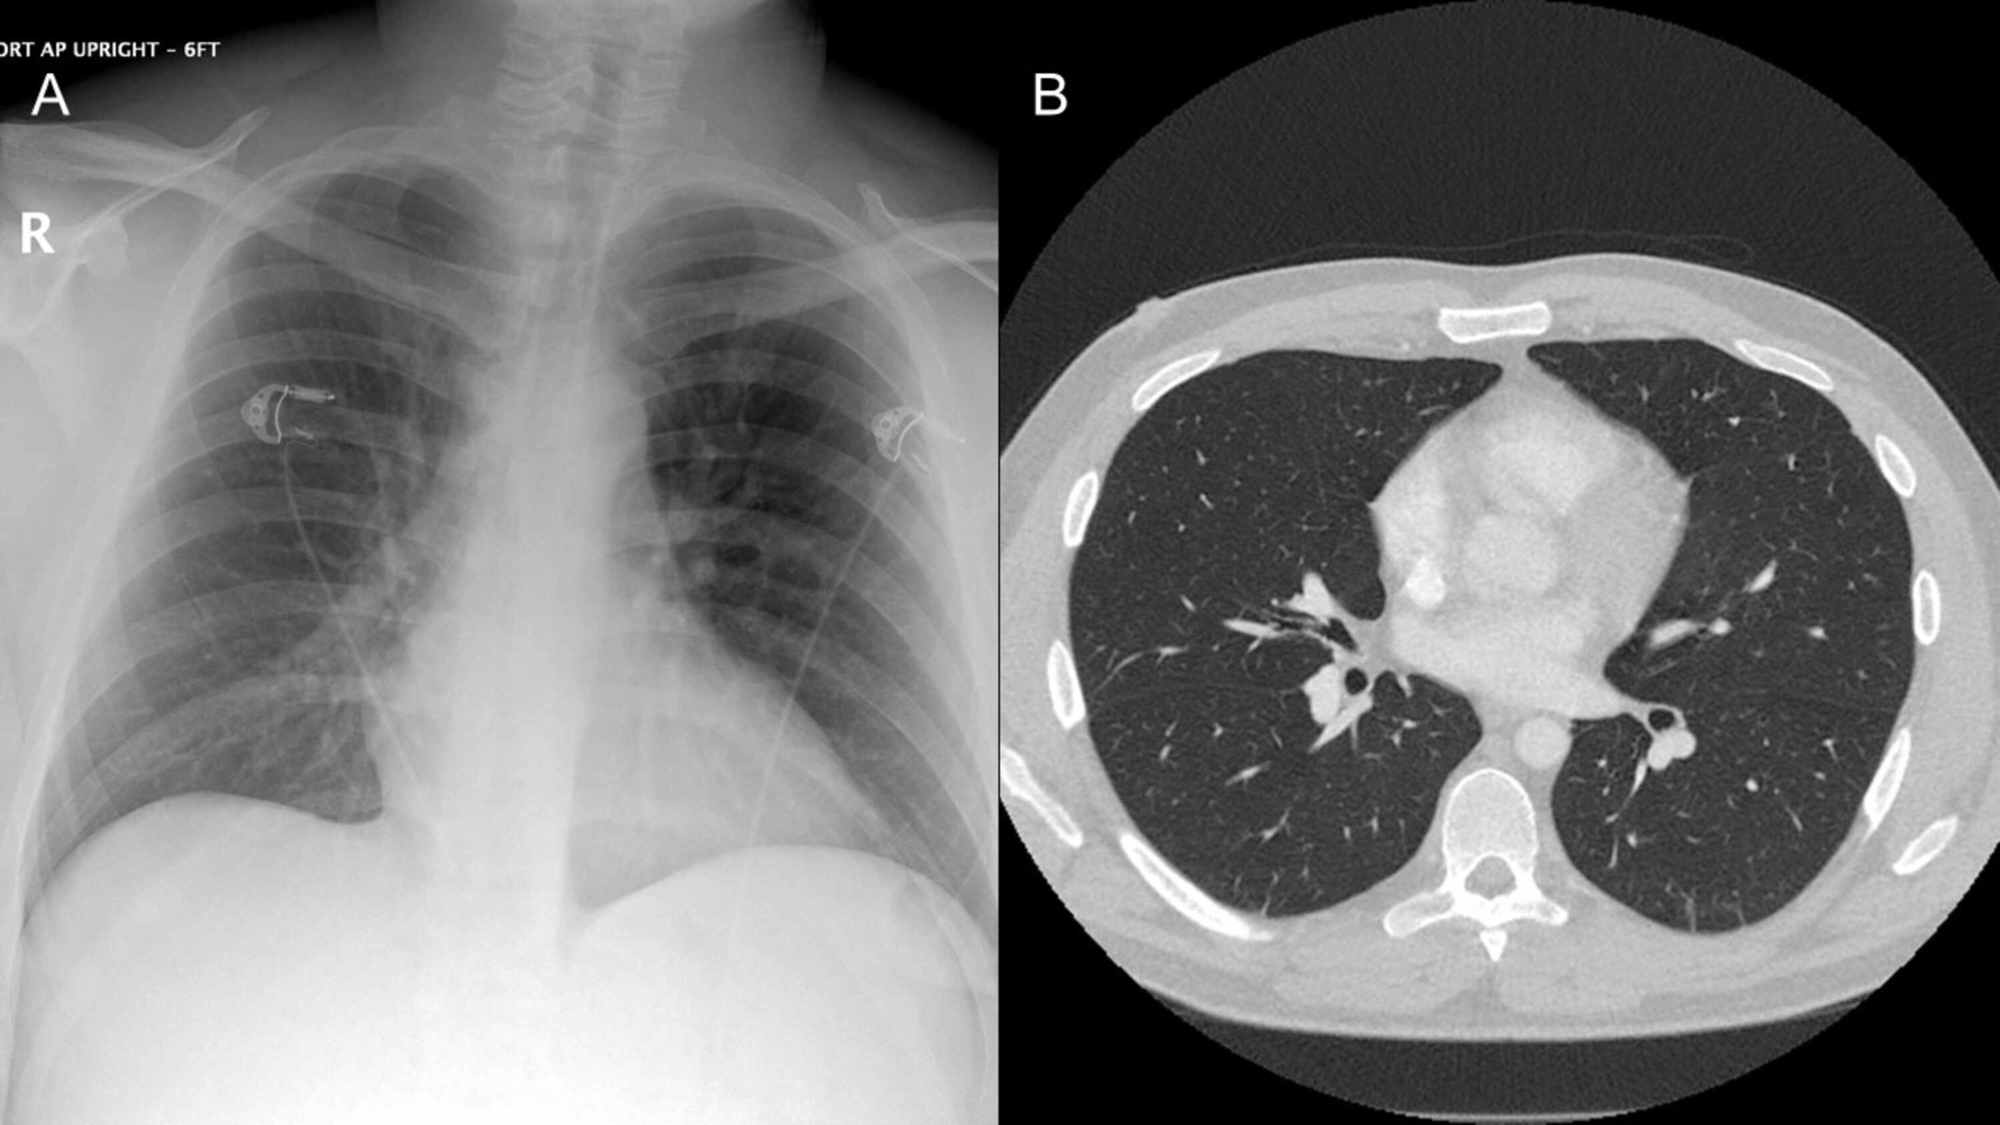

Cureus Primary Pulmonary Hodgkin's Lymphoma A Rare Etiology of a Chest X-Ray To Diagnose Leukemia Consider seeking medical care if you have developed any of these. It is used to look for: — physical exams for diagnosing leukemia. — myeloid sarcoma. Although the thorax is uncommonly involved, it may occur in the lungs, pleura, mediastinum, chest. a ct scan of the chest or abdomen can help detect an enlarged lymph node or. Chest X-Ray To Diagnose Leukemia.

From www.cureus.com